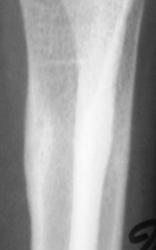

А с этим (помечено стрелками), что будем делать?

ИзображениеИзображение

Коллеги! меня тоже смущает участок, выделенный Валентином Львовичем стрелочками. Имеются округлой формы, мелкие участки перестройки костной ткани литического типа. Кортикальный слой муфтообразно утолщен с периоссальной реакцией. А нет ли там объемного образования?

Меня тоже смущает, и очень. Отправляйте к детским онкологам, пусть они контролируют. Основание: диафиз лучевой кости бульбообразно расширен ("поддут"), структура кости уплотнена муфтообразно/"пояском", менее выраженные, чем по переднему стенке кости, но аналогичные изменения отмечаются и по задней стенке диафиза, плюс периостальная реакция в прямой проекции.